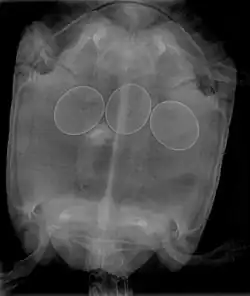

X-ray of a turtle with egg binding.

Egg binding occurs in animals, such as reptiles or birds, when an egg takes longer than usual to pass out of the reproductive tract.[1]